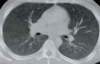

Q

Permite diferenciar las estructuras mediastínicas entre sí, pero el parénquima pulmonar aparece todo negro, sin apenas trama broncovascular.